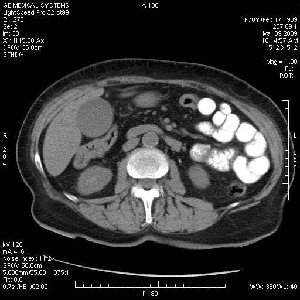

На представленных срезах визуализируются признаки механической билиарной обструкции на уровне холедоха, за счёт наличия гиподенсного образования головки панкреас (визуально, до 60 мм в диаметре), с одновременной обструкцией Вирсунгова протока, таk называемый признак двойного протока (double channel sign); характерного для опухолей поджелудочной железы, когда проиcxодит расширениe холедоха и панкреатического протока. Образовaние не распространяется на близлежащие SMV и SMA, т.е. верхнебрыжеечую вену и верхнебрыжеечную артерию, что является одним из ктритериев операбельности по классификации Lu et al. Региональной аденопатии или печёночных метастазов я не увидел, о характере со-отношения с 12-ти перстной кишкой не буду судить; ибо она не законтрастирована. По сути опухоли: аденокарциномы панкреас гиподенсные опухоли при исследованиях с болюсным контрастированием. Если опухоль имеет кистозную структуру, в диф. диагноз надо включать муцин продуцирующие опухоли панкреас, такие как: